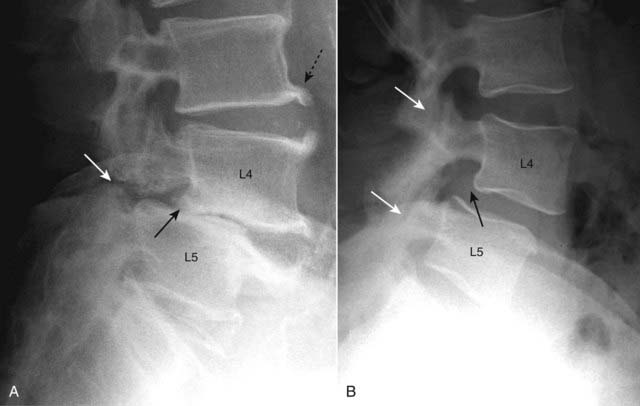

imageOn lateral (sagittal) imaging of the cervical spine, the inferior articular facets will lie in front of the superior facets of the body below. This is the reverse of the normal anatomic relationship between adjacent facets (Fig. 24-21).

image Since the superior articular facets are no longer “covered” by the inferior facets above them, this appearance was described on CT as the naked facet sign.

Figure 24-21 Normal and bilateral locked facets.

A, Normally, the inferior articular facet of the body above (in this case C4, solid white arrow) lies posterior to the superior articular facet of the body below (in this case C5, solid black arrow). B, The inferior articular facet of C4 (dotted white arrow) lies anterior to the superior articular facet of C5 (dotted black arrow), the reverse of normal. Locking of the facets in the cervical spine can occur as a result of a hyperflexion injury that results in forward slippage of the affected vertebral body on the body below it by at least 50% of its AP diameter (solid white arrow).